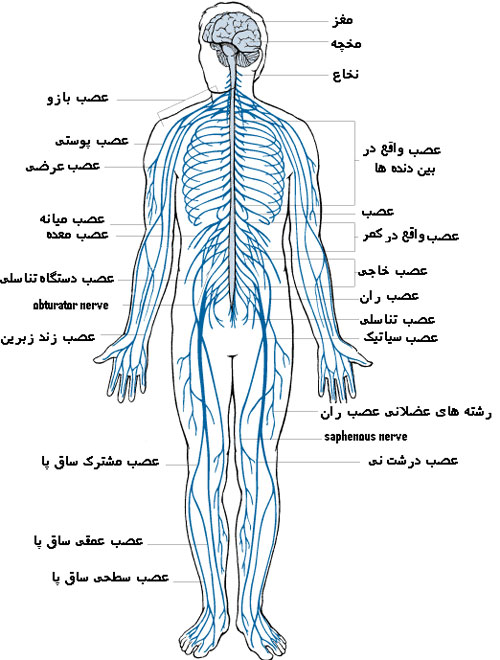

قیمت: 68٬000 تومان - دسته بندی فایل: پاورپوینتپاورپوینت دستگاه عصبی یا سیستم عصبی یا سامانهٔ عصبی

فروش ویژه پاورپوینت حرفه ای دستگاه عصبی یا سیستم عصبی یا سامانهٔ عصبی با تخفیف استثنایی فقط 72 هزار تومان تعداد اسلاید : 32 اسلاید